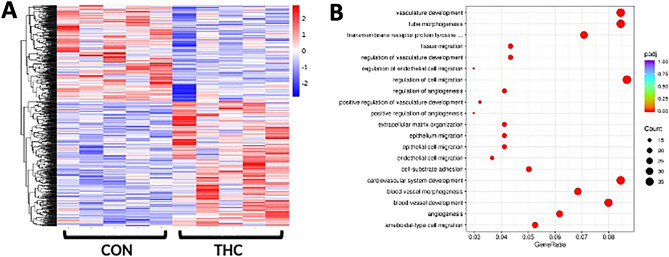

RNA sequencing

Applying a false discovery rate analysis (p < 0.05), in THC-exposed compared to controls, we identified 426 upregulated genes and 327 downregulated genes (Supplemental Table 1). Hierarchical clustering analysis was performed on differentially expressed genes to identify a distinct gene expression signature in THC-exposed placentas when compared to control placentas (Fig. 5A). In THC-exposed placentas, we further identified 101 genes with p-value < 0.05 and fold-change > 1.5. Comparing THC-exposed placentas to control placentas, pathways with p < 0.001 are shown in Fig. 5B. Gene Ontology (GO) pathway analysis showed significant enrichment in DEGs involved in cytokine binding, regulation of cell migration, cell-substrate adhesion, angiogenesis, and vascular development (Fig. 5B). Similarly, KEGG pathway analysis showed enrichment in DEGs regulating cell migration.

Our RNA sequencing findings were notable for involvement of angiogenesis and vascular pathways. Taken together with the histologic changes in THC-exposed placentas, these data suggest that prenatal THC exposure not only changes the structure of the placenta but also significantly alters gene expression in pathways regulating cell migration and vascular development. A recently published human cohort of maternal cannabis use reduced expression of placental genes involved in immune system function including type 1 interferon, neutrophil, and cytokine-signaling pathways23. Specifically, this study demonstrated decreased expression of immune genes, including hyperactivity-linked genes IL1B and CXCL8, and S100A823. Similarly, our study was notable for increased expression of IL1RN, an IL1 receptor antagonist, and decreased expression of genes in the S100 protein family.